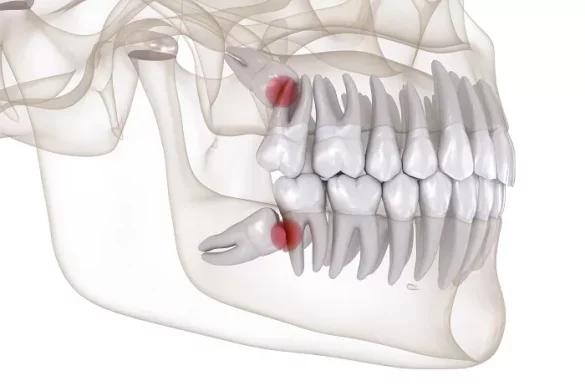

One of the most common issues with wisdom teeth is impaction. An impacted wisdom tooth is one that fails to fully emerge through the gum line. It can be partially impacted, where only a portion of the tooth is visible, or fully impacted, remaining completely beneath the gum and bone. Impacted wisdom teeth can cause a range of problems. They may push against adjacent teeth, leading to crowding and misalignment of the existing teeth. This can disrupt the overall alignment of the dental arch and may require orthodontic intervention to correct.

For example, if a lower wisdom tooth is angled sideways and pushing against the second molar, it can cause the second molar to shift out of its proper position. This can affect the bite and lead to difficulties in chewing and potential damage to the teeth over time.

Wisdom teeth that erupt at an incorrect angle or are rotated can also cause issues. They may not fit properly within the dental arch and can create spaces where food particles can get trapped. These trapped food particles are difficult to clean and can lead to an increased risk of tooth decay and gum disease. The abnormal position of the wisdom teeth can also irritate the surrounding gum tissue, causing inflammation and pain.

A wisdom tooth that is rotated 90 degrees, for instance, may have a large surface area in contact with the adjacent tooth, making it impossible to clean effectively. Bacteria can build up in this area, leading to cavities on both the wisdom tooth and the neighboring tooth.